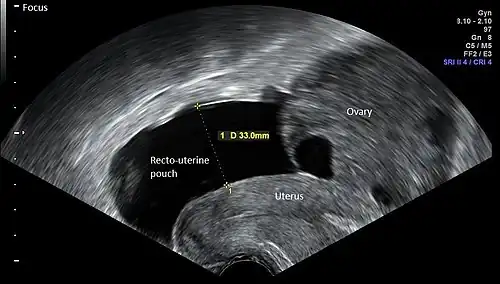

|   Vaginal ultrasonography in the sagittal plane in a woman with mild OHSS, showing a 33 mm wide anechogenic area behind the uterus in the recto-uterine pouch, which means there was ascites, that is, free fluid in the peritoneal cavity. Normally, there is up to 5 ml of fluid in the recto-uterine pouch,[5] corresponding approximately to an area up to 10 mm wide. The ovary measured up to 6.5 cm in diameter. |